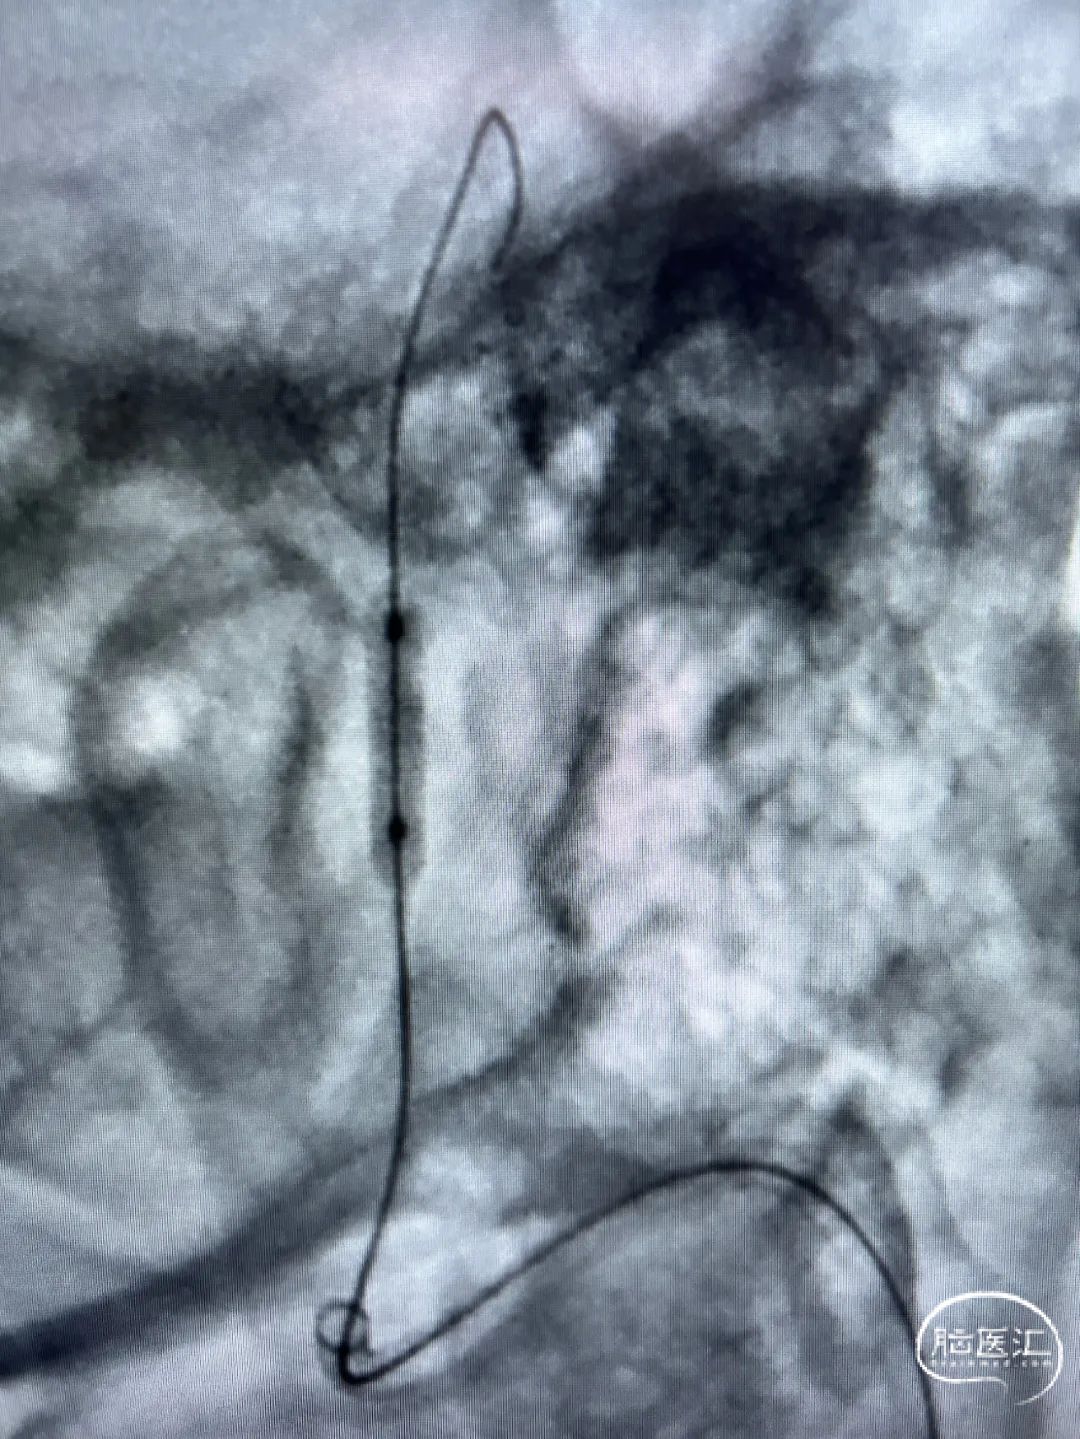

路图下,超滑导丝引导下端通桥银蛇®Plus远端通路导管到位。

路图下,通桥x海思北斗神经微导丝顺利通过右侧椎动脉V4段狭窄处。

颅内球囊导管输送到位,通桥x海思北斗神经微导丝支撑稳定。

颅内球囊缓慢充分扩张狭窄段。

球囊扩张后多角度造影局部狭窄及前向血流较术前明显改善。